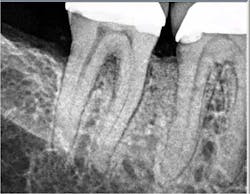

The patient returned for a postop appointment at 5.5 months and a new radiograph (figure 5) and clinical photographs (figures 6 and 7) were taken. Excellent regeneration is evident at both sites radiographically and clinically. New periodontal charting was done (figure 8) showing near-complete regeneration of the intrabony defect on the distal of No. 30 and a great improvement in the furcation of No. 31. There is no bleeding or inflammation present at this time.